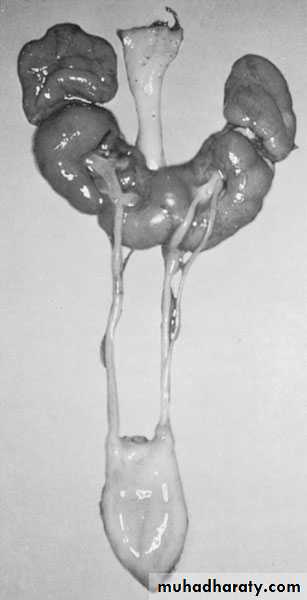

Crossed Renal Ectopia With and Without FusionHorseshoe Kidney

Found in 1:1000 necropsies and is more common in men.probably the most common of all renal fusion anomalies

The anomaly consists of two distinct renal masses lying vertically on either side of the midline and connected at their respective lower poles by a parenchymatous or fibrous isthmus that crosses the midplane of the body.

Fusion of the renal masses occurs early in embryonic life, so its ascent will be impeded by inferior mesenteric artery.

The kidneys are low located, mal rotated and pelves lie anteriorly